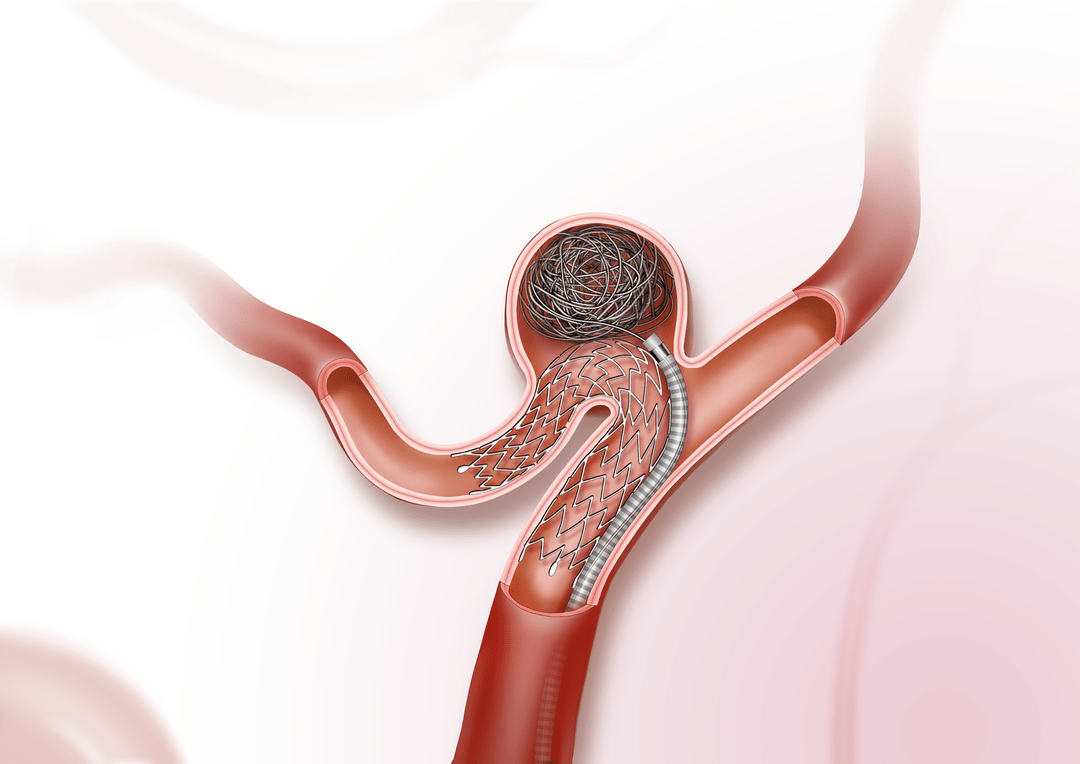

支架结合弹簧圈技术,治疗宽颈动脉瘤

neuroform atlas支架是一款激光雕刻的开环支架,最近应用于临床与弹簧

neuroform atlas支架作为一种小口径支架,由于可以通过0.